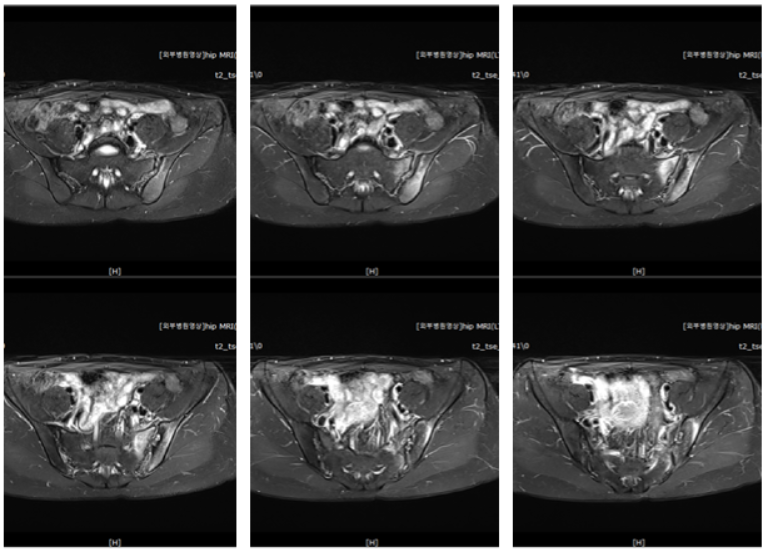

신경학적 검사상에 좌측 천장관절염을 의심하게하는 압통을 비롯한 소견을 보였고, 방사선소견상에는 골반이 많이 틀어져있으며 좌측 천장관절에 방사선 불투과성(radiopaque) 변화 소견이 있었습니다. 환자분은 3시간정도 차를 타고 가야하는 거리에서 오셨고, 10년 가까이 만성통증에 시달리는 분이라 정확한 진단이 필요하여 MRI 검사를 시행하였습니다.

골반MRI 검사상에는 좌측 천장관절염이 진단되었습니다.